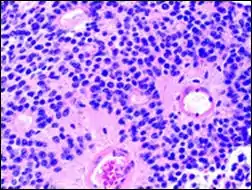

Perivascular pseudorosette

A perivascular pseudorosette consists of a spoke-wheel arrangement of cells with tapered cellular processes radiates around a wall of a centrally placed vessel. The modifier “pseudo” differentiates this pattern from the Homer Wright and Flexner-Wintersteiner rosettes, perhaps because the central structure is not actually formed by the tumor itself, but instead represents a native, non-neoplastic element. Also, some early investigators argued about the definition of a central lumen, choosing “pseudo” to indicate that the hub was not a true lumen but contained structures. Nevertheless, this pattern remains extremely diagnostically useful and the modifier unnecessarily leads to confusion. Perivascular pseudorosettes are encountered in most ependymomas regardless of grade or variant. As such, they are significantly more sensitive for the diagnosis of ependymomas than true ependymal rosettes. Unfortunately, perivascular pseudorosettes are also less specific in that they are also encountered in medulloblastomas, PNETs, central neurocytomas, and less often in glioblastomas, and a rare pediatric tumor, monomorphous pilomyxoid astrocytomas.[2]

- Micrograph of perivascular pseudorosettes